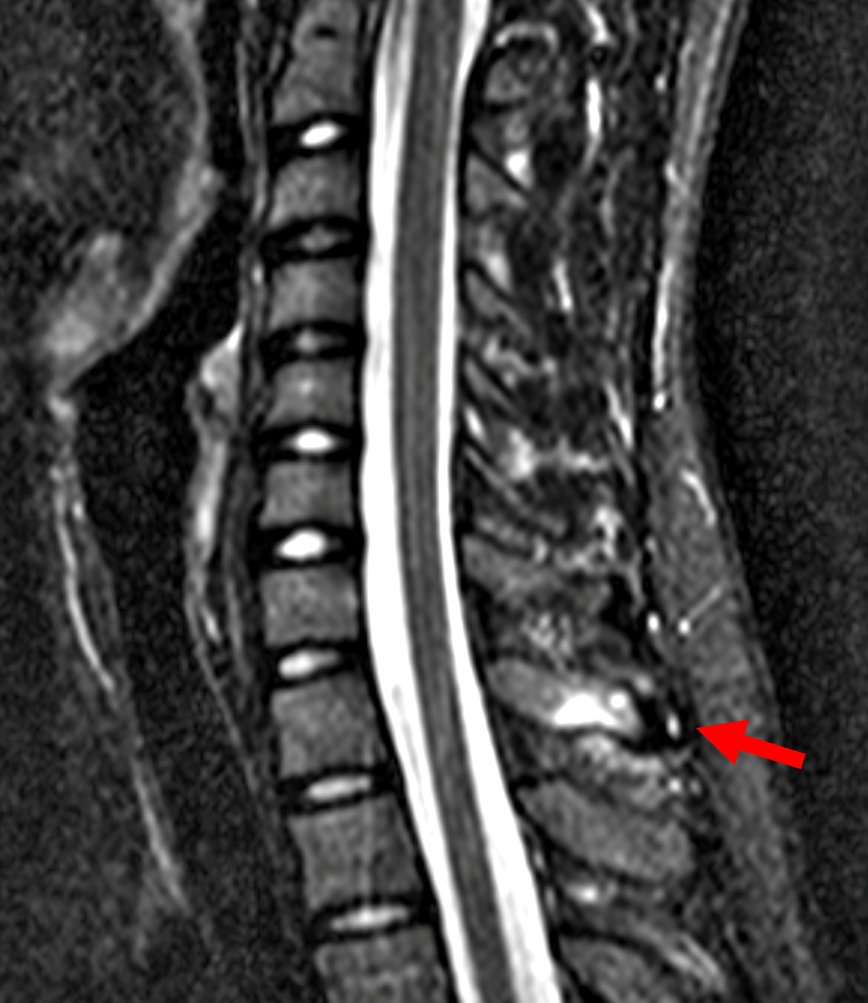

Young gentleman came with severe low back ache following an episode of dengue fever. What do we see here? #spineimaging #medtwitter #radtwitter #FOAMrad #neuroimaging @drvenkimdrd